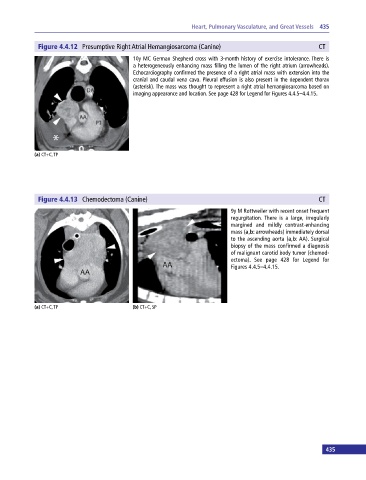

Figure 4.4.12 Presumptive Right Atrial Hemangiosarcoma (Canine) CT

10y MC German Shepherd cross with 3‐month history of exercise intolerance. There is

a heterogeneously enhancing mass filling the lumen of the right atrium (arrowheads).

Echocardiography confirmed the presence of a right atrial mass with extension into the

cranial and caudal vena cava. Pleural effusion is also present in the dependent thorax

(asterisk). The mass was thought to represent a right atrial hemangiosarcoma based on

imaging appearance and location. See page 428 for Legend for Figures 4.4.5–4.4.15.

Figure 4.4.13 Chemodectoma (Canine) CT

9y M Rottweiler with recent onset frequent

regurgitation. There is a large, irregularly

margined and mildly contrast‐enhancing

mass (a,b: arrowheads) immediately dorsal

to the ascending aorta (a,b: AA). Surgical

biopsy of the mass confirmed a diagnosis

of malignant carotid body tumor (chemod-

ectoma). See page 428 for Legend for

Figures 4.4.5–4.4.15.